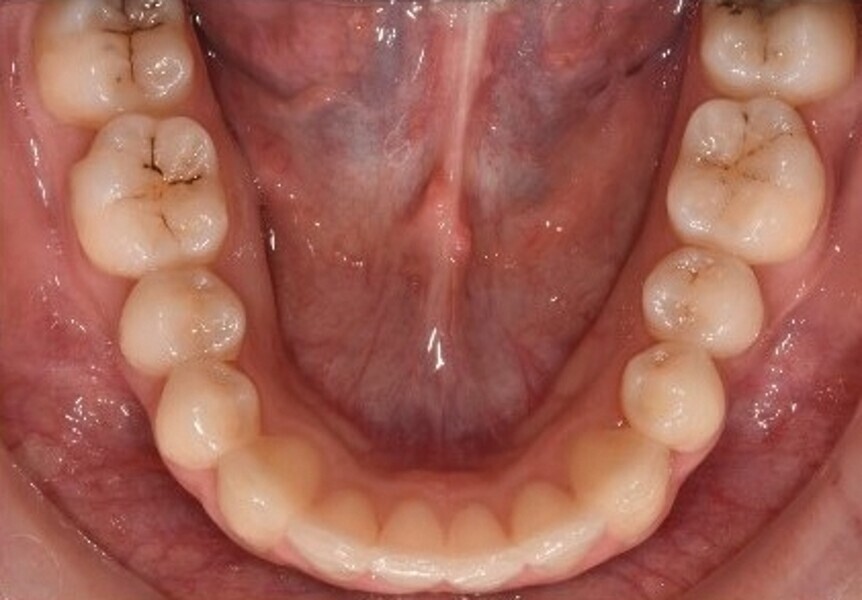

Après une période de onze mois et un nombre total de 66 aligneurs maxillaires et mandibulaires, le traitement est terminé et tous les objectifs sont atteints, à savoir une relation bilatérale de Classe I, une symétrie des arcades et la correction de l’encombrement (Fig. 6).

Fig. 6a : Photographie intraorale finale.

Fig. 6b : Photographie intraorale finale.

Fig. 6c : Photographie intraorale finale.

Fig. 6d : Photographie intraorale finale.

Fig. 6e : Photographie intraorale finale.

La radiographie panoramique finale (Fig. 7) montre des racines parallèles et l’absence de tout signe de résorption radiculaire (bien que seules des radiographies périapicales pourraient confirmer ceci). Selon l’analyse céphalométrique, les incisives maxillaires et mandibulaires ont conservé leur position (position initiale de l’incisive mandibulaire à la ligne A-pogonion (A-Pog) : 14 mm ; position finale de l’incisive mandibulaire à la ligne A-Pog : 13 mm. Fig. 8 )